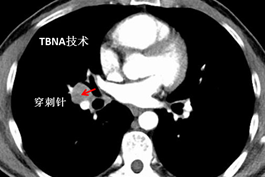

病例二:

(胸部增强CT提示肿块在右中下叶支气管管腔外)

(通过CT片测得病灶于标记点的距离,确定进针角度及深度)